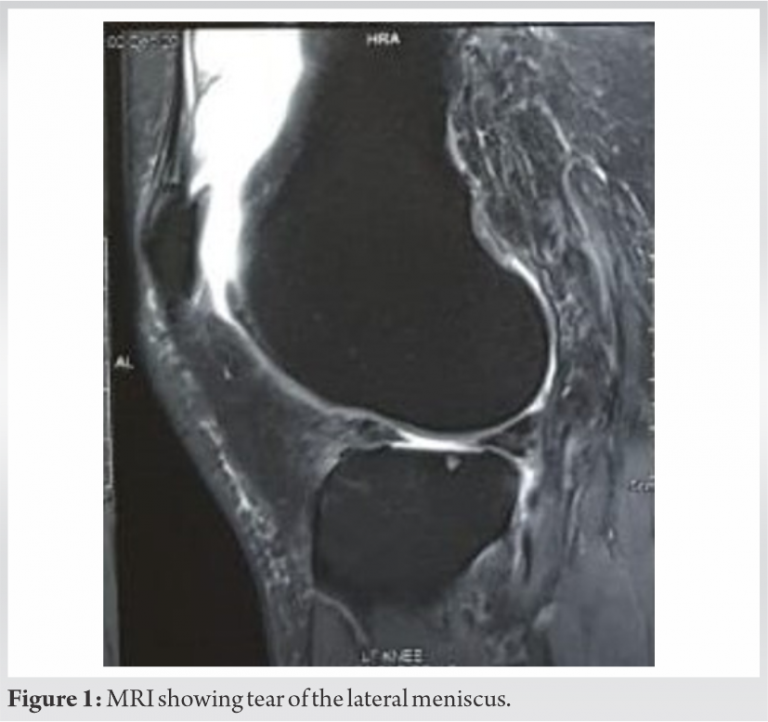

A 50-year-old woman came with chief complaints of pain and swelling in the left knee. She had a recent history of twisting injury while walking. Physical examination revealed tenderness along the lateral joint line and McMurray’s test was positive for lateral meniscus. Flexion was terminally restricted and painful. Radiographs showed evidence of lateral compartment osteoarthritic changes. Tear of lateral meniscus (Fig. 1) along with synovitis (Fig. 2) and degenerative changes in the cartilage were evident on magnetic resonance imaging (MRI) of the left knee. Arthroscopic partial meniscectomy was planned on the basis of her clinical and radiological presentation.